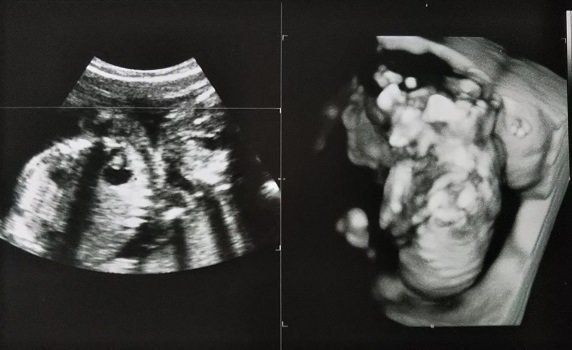

妊娠19週目のエコー写真 赤ちゃんの心室や膀胱の様子もエコーで確認できました。

妊娠19週目。性別がわかるかもしれないということで、主人も一緒について来た健診のときのエコー写真です。エコーを見せてもらって、先生から「心臓の部屋は4つ。膀胱におしっこも溜まっているから、腎臓にも異常なし。背骨もしっかりしていて体重等も標準。いい子です」と言っていただいてひと安心。帰りの車で主人に「先生、女の子って言っていたね」と言われてビックリ!聞き逃していた…。主人曰く「先生は女の子でまちがいないとも言っていたよ」とのこと。帰りに本屋さんに寄って、女の子の名前辞典を買いました。